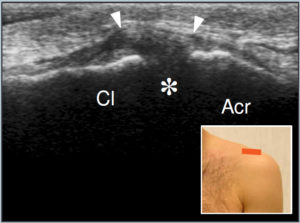

← MSK ULTRASOUND – SHOULDER